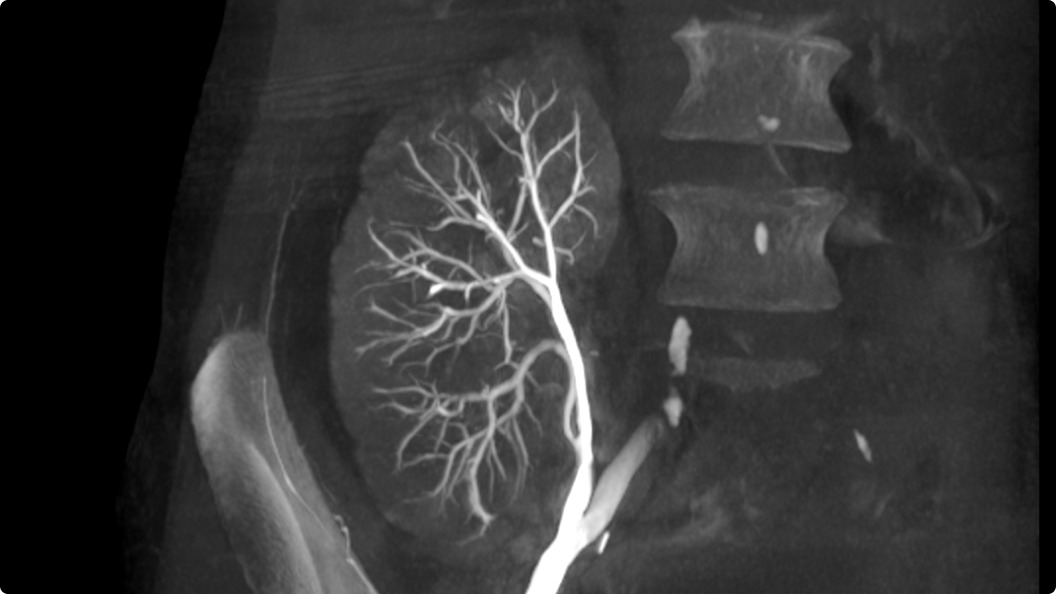

Die Cone-Beam-Computertomographie (CBCT) ist eine fortschrittliche Bildgebungstechnologie, die neue Maßsäbe in der medizinischen Diagnostik setzt. Sie liefert hochauflösende, dreidimensionale Aufnahmen in Echtzeit - für mehr Präzision, Sicherheit und Vertrauen in der klinischen Entscheidungsfindung.

Präzision: Detaillierte 3D-Bildgebung ermöglicht eine exakte Diagnostik und gezielte Behandlungsplanung, auch bei komplexen Fragestellungen.

Vielseitigkeit: CBCT unterstützt eine Vielzahl interventioneller und diagnostischer Anwendungen - von Leber und Gehirn bis zur Prostata und darüber hinaus.

3D CT HD5 ist eine Option, die auf fortschrittlichen Algorithmen basiert. Diese Algorithmen verbessern die Visualisierung von Weichgewebe, reduzieren Rauschen und minimieren Artefakte, die den Visualisierungskomfort beeinträchtigen können. 3D CT HD bietet eine qualitativ hochwertige Bildgebung von internen Körperstrukturen einschließlich Gefäßen, Knochen und Weichgewebe. Mit dieser Funktion können Ärzte auf Aufnahmen von hoher Qualität zugreifen und fundierte Entscheidungen treffen.